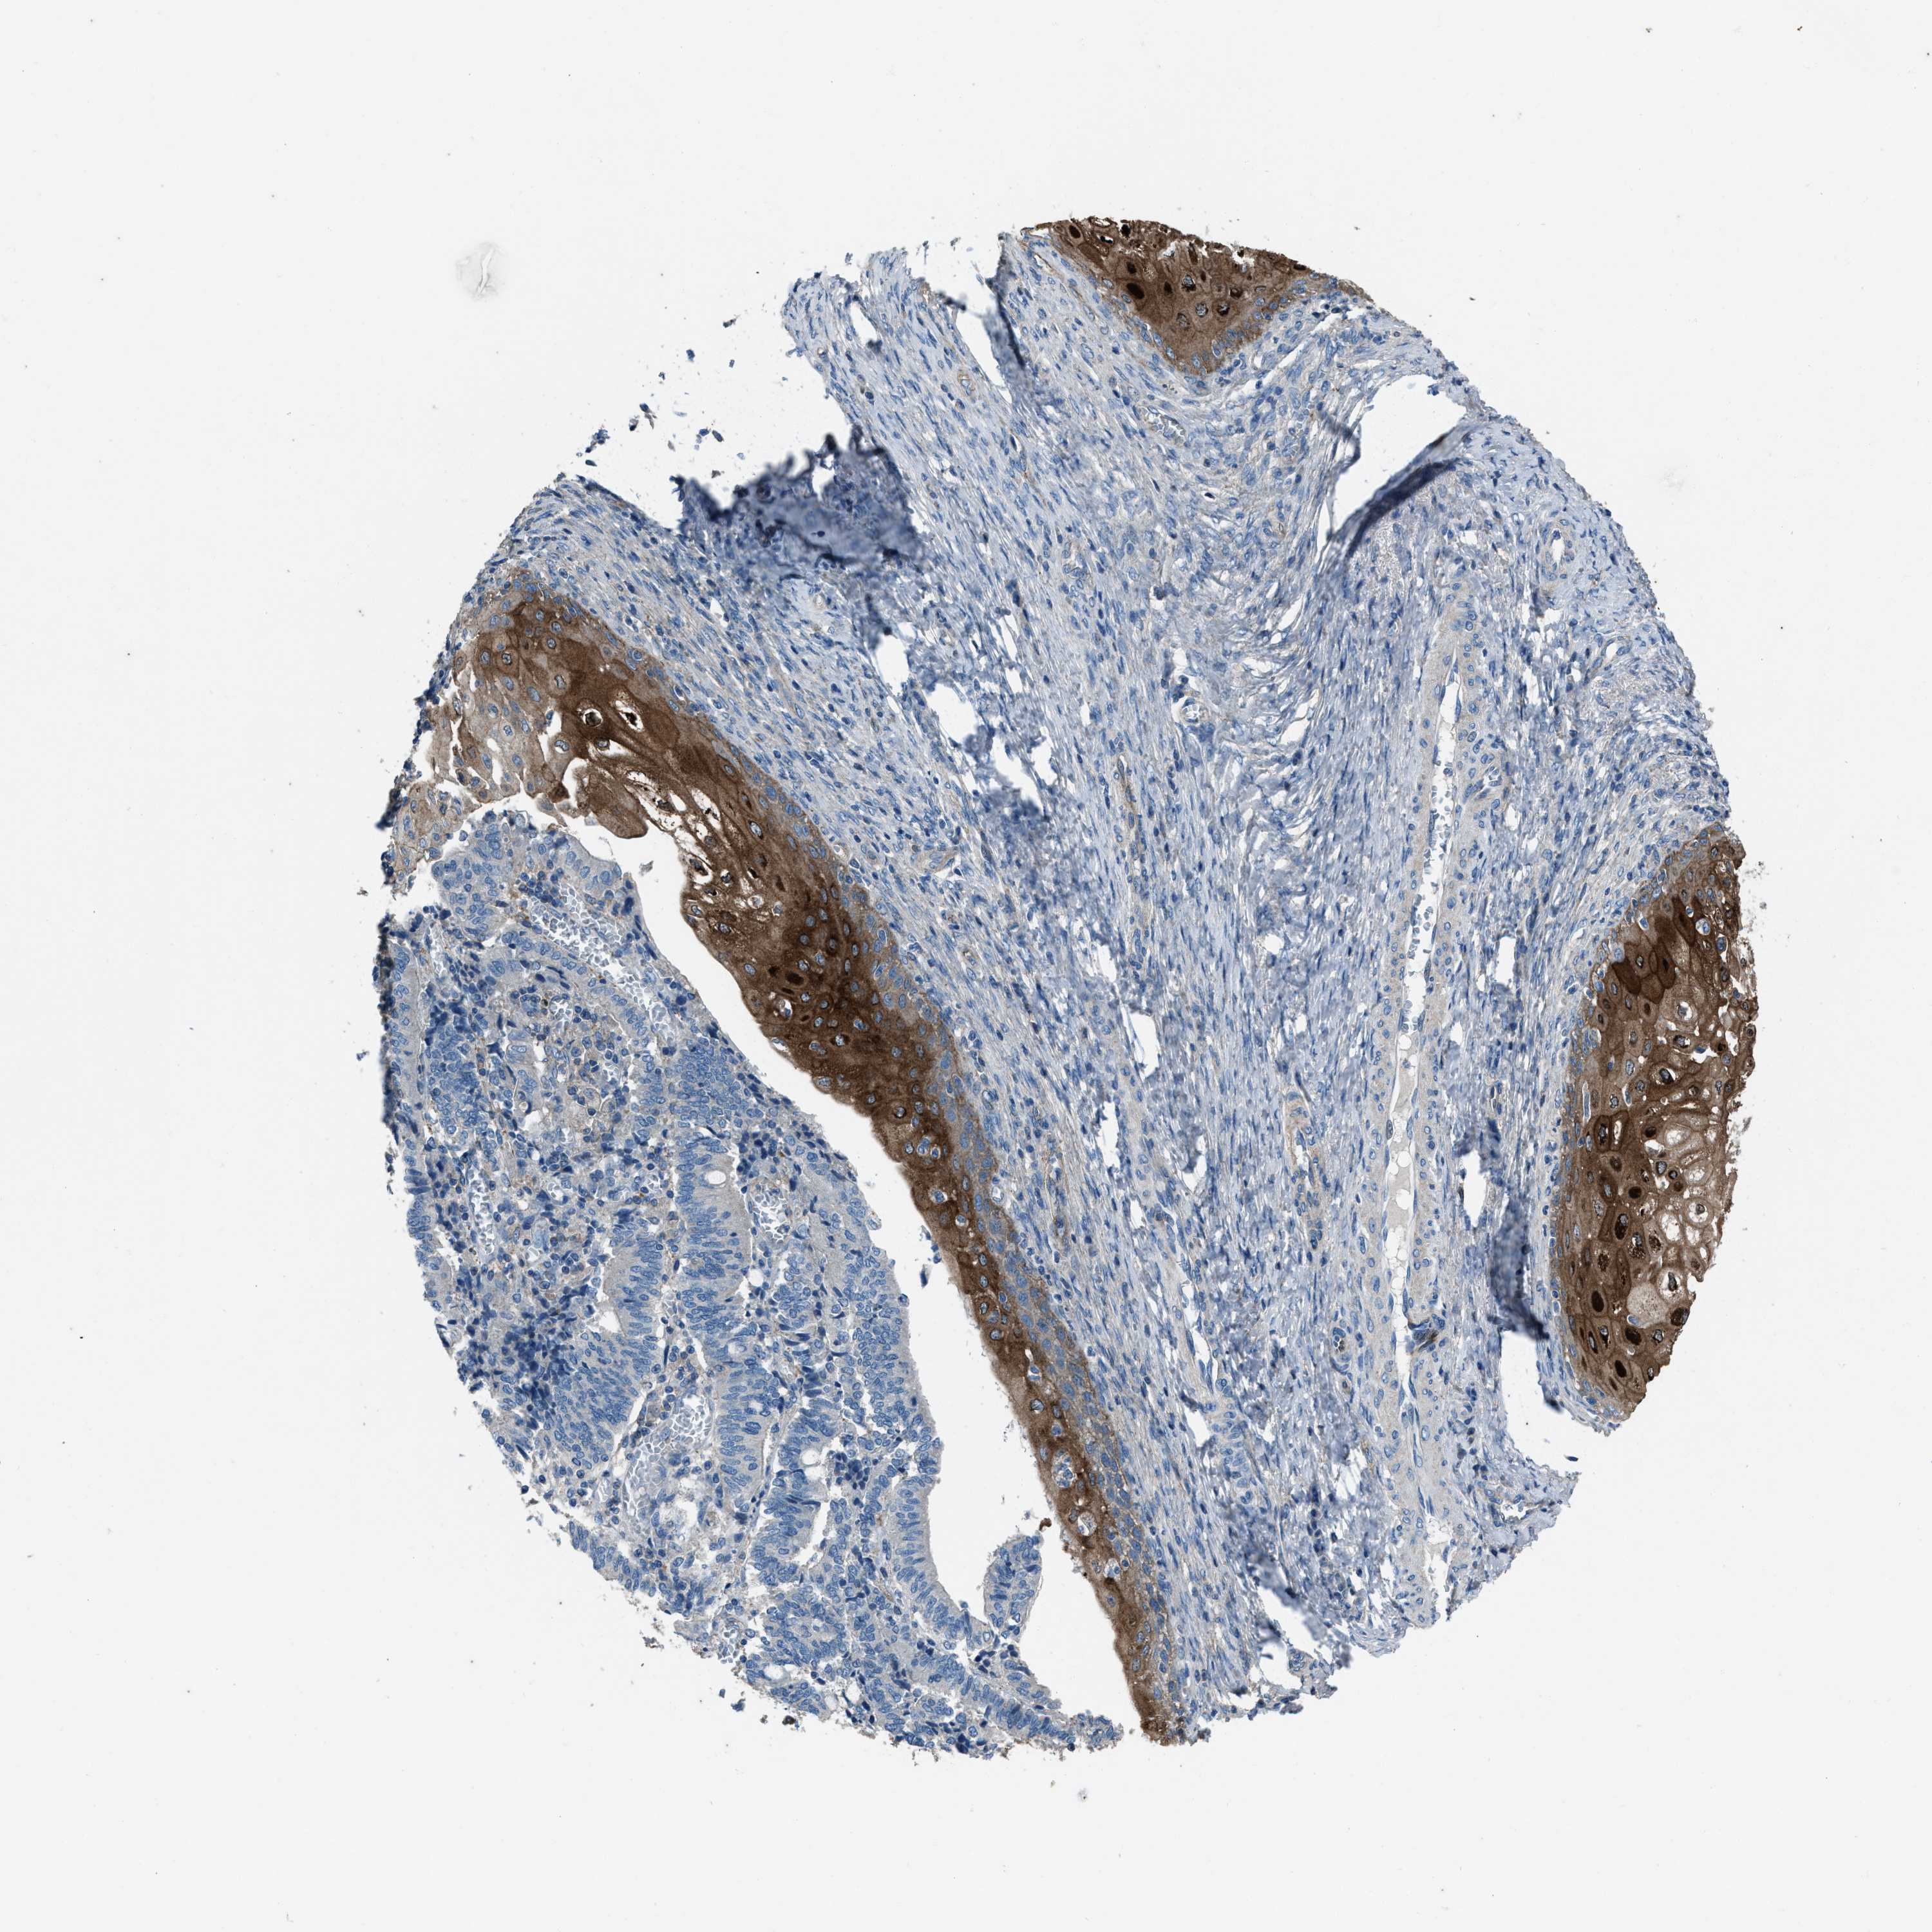

CERVICAL CANCER - Protein expressioni

A mouse-over function shows sample information and annotation data. Click on an image to view it in a full screen mode. Samples can be filtered based on level of antibody staining by selecting one or several of the following categories: high, medium, low and not detected. The assay and annotation is described here.

Note that samples used for immunohistochemistry by the Human Protein Atlas do not correspond to samples in the TCGA dataset.

Antibody stainingi

Antibody staining in the annotated cell types in the current human tissue is reported as not detected, low, medium, or high, based on conventional immunohistochemistry profiling in selected tissues. This score is based on the combination of the staining intensity and fraction of stained cells.

Each image is clickable and will lead to virtual microscopy that enables deeper exploration of all samples and also displays staining intensity scores, fraction scores and subcellular localization as well as patient and tissue information for each sample.

Antibody HPA020095

Antibody HPA020138

Antibody CAB010878

Antibody CAB080402

Staining

High

Medium

Low

Not detected

Intensity

Strong

Moderate

Weak

Negative

Quantity

>75%

75%-25%

<25%

None

Location

Nuclear

Cytoplasmic/membranous

Cytoplasmic/membranous,nuclear

Squamous cell carcinoma, NOS

Adenocarcinoma, NOS